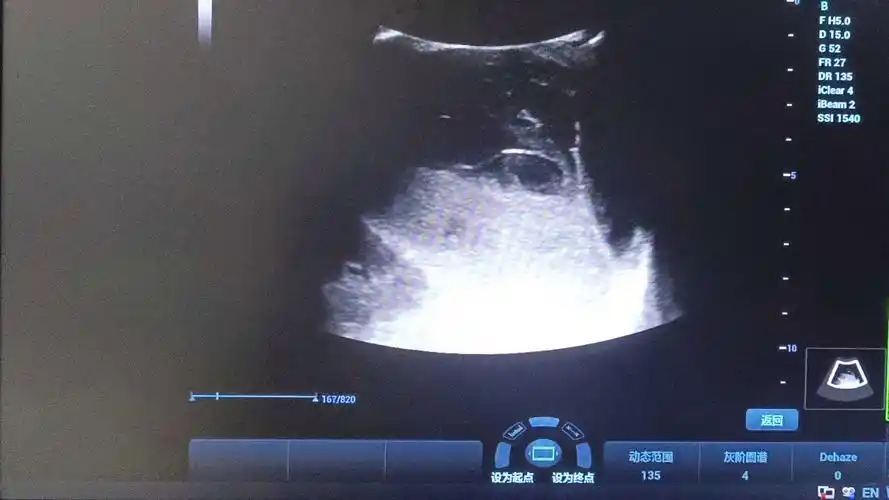

快递小哥连续工作12小时摔倒致脾脏破裂新华医院紧急手术

【病例夹】当脾破裂遇到腹腔镜微创手术_王先生_脾脏_损伤

ct提示:脾脏破裂.jpg

脾脏创伤性破裂一例